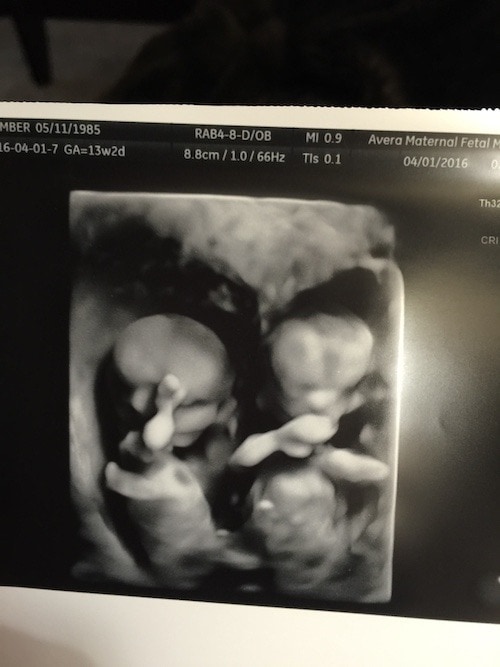

- Ultrasound Photos at 13 Weeks Pregnant With Twin

Ultrasound Photos at 13 Weeks Pregnant With Twin